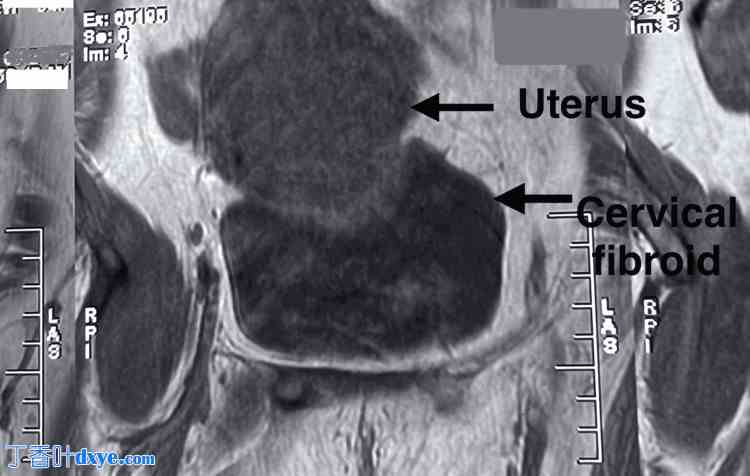

一般体格检查发现患者面色苍白。实验室检查显示血红蛋白水平为 4.1 g/dL,脉搏 110 次/分,收缩压 86 mmHg。MRI 显示子宫大小为 6.3 x 7.6 cm,子宫下段可见一个 10 x 10 cm 的异质性肿块,提示为子宫肌瘤,如图 12 所示。双侧附件未见异常。

图 12. MRI 显示子宫大小为 6.3 x 7.6 cm,子宫下段可见一个 10 x 10 cm 的异质性肿块,提示为宫颈肌瘤。